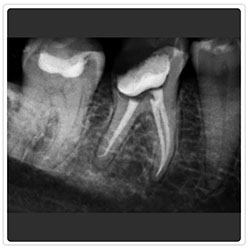

Solución de Rayos-X Intraorales New IDA

La imagen de la evolución

New IDA es el sensor digital intraoral de la linea Eagle Image con soluciones eficientes de las imágenes para un diagnóstico más nítido, preciso y seguro.

Los cuidados de la salud bucal han alcanzado un modo más avanzado.

Optimice su tiempo, tómese sus radiografías con New Ida en OEP.

Radiografía Retroalveolar

Radiografía Control Endodoncia

Radiografía Intraoral

Radiografía Control de Implante